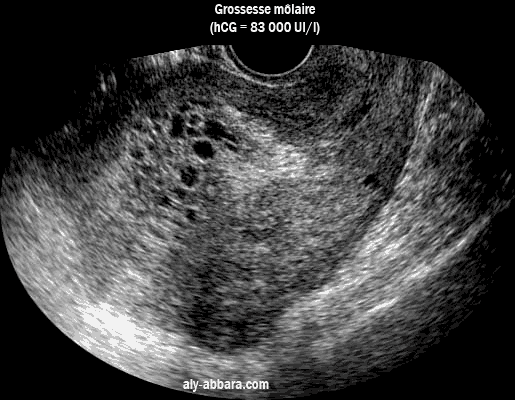

Une coupe sagittale d'un utérus contenant une grossesse môlaire avec son aspect vésiculaire typique.

Image échographique montrant une coupe sagittale d'un utérus contenant une grossesse môlaire

avec l'aspect vésiculaire typique de la môle

On remarque bien l'absence de structures embryonnaires ou préplacentaires reconnaisables